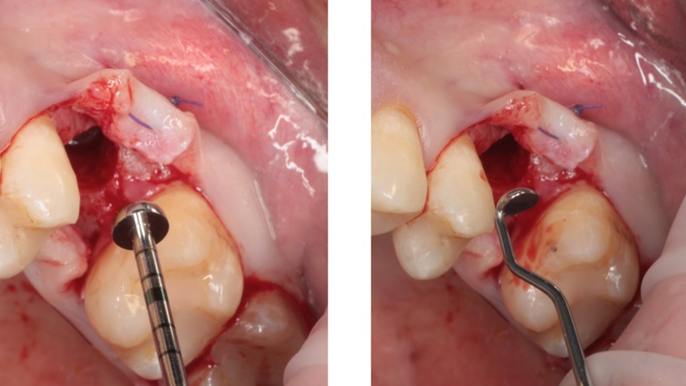

“Thin ridge expansion with minimally invasive surgery!

Use SmarThor & AnyRidge to place a wider diameter implant with minimal drilling after ridge splitting, even in thin ridge under 2mm! “

Clinical case: Ridge splitting technique using SmarThor + AnyRidge as expander

- Courtesy of Dr.Kwang-Bum Park, Korea -

AnyRidge, ridge splitting, GBR, Dr. Kwang-Bum Park, mandibular posterior, SmartThor, Mega-Oss, thin ridge, bone regeneration

AnyRidge implant system. SmarThor, Mega-Oss